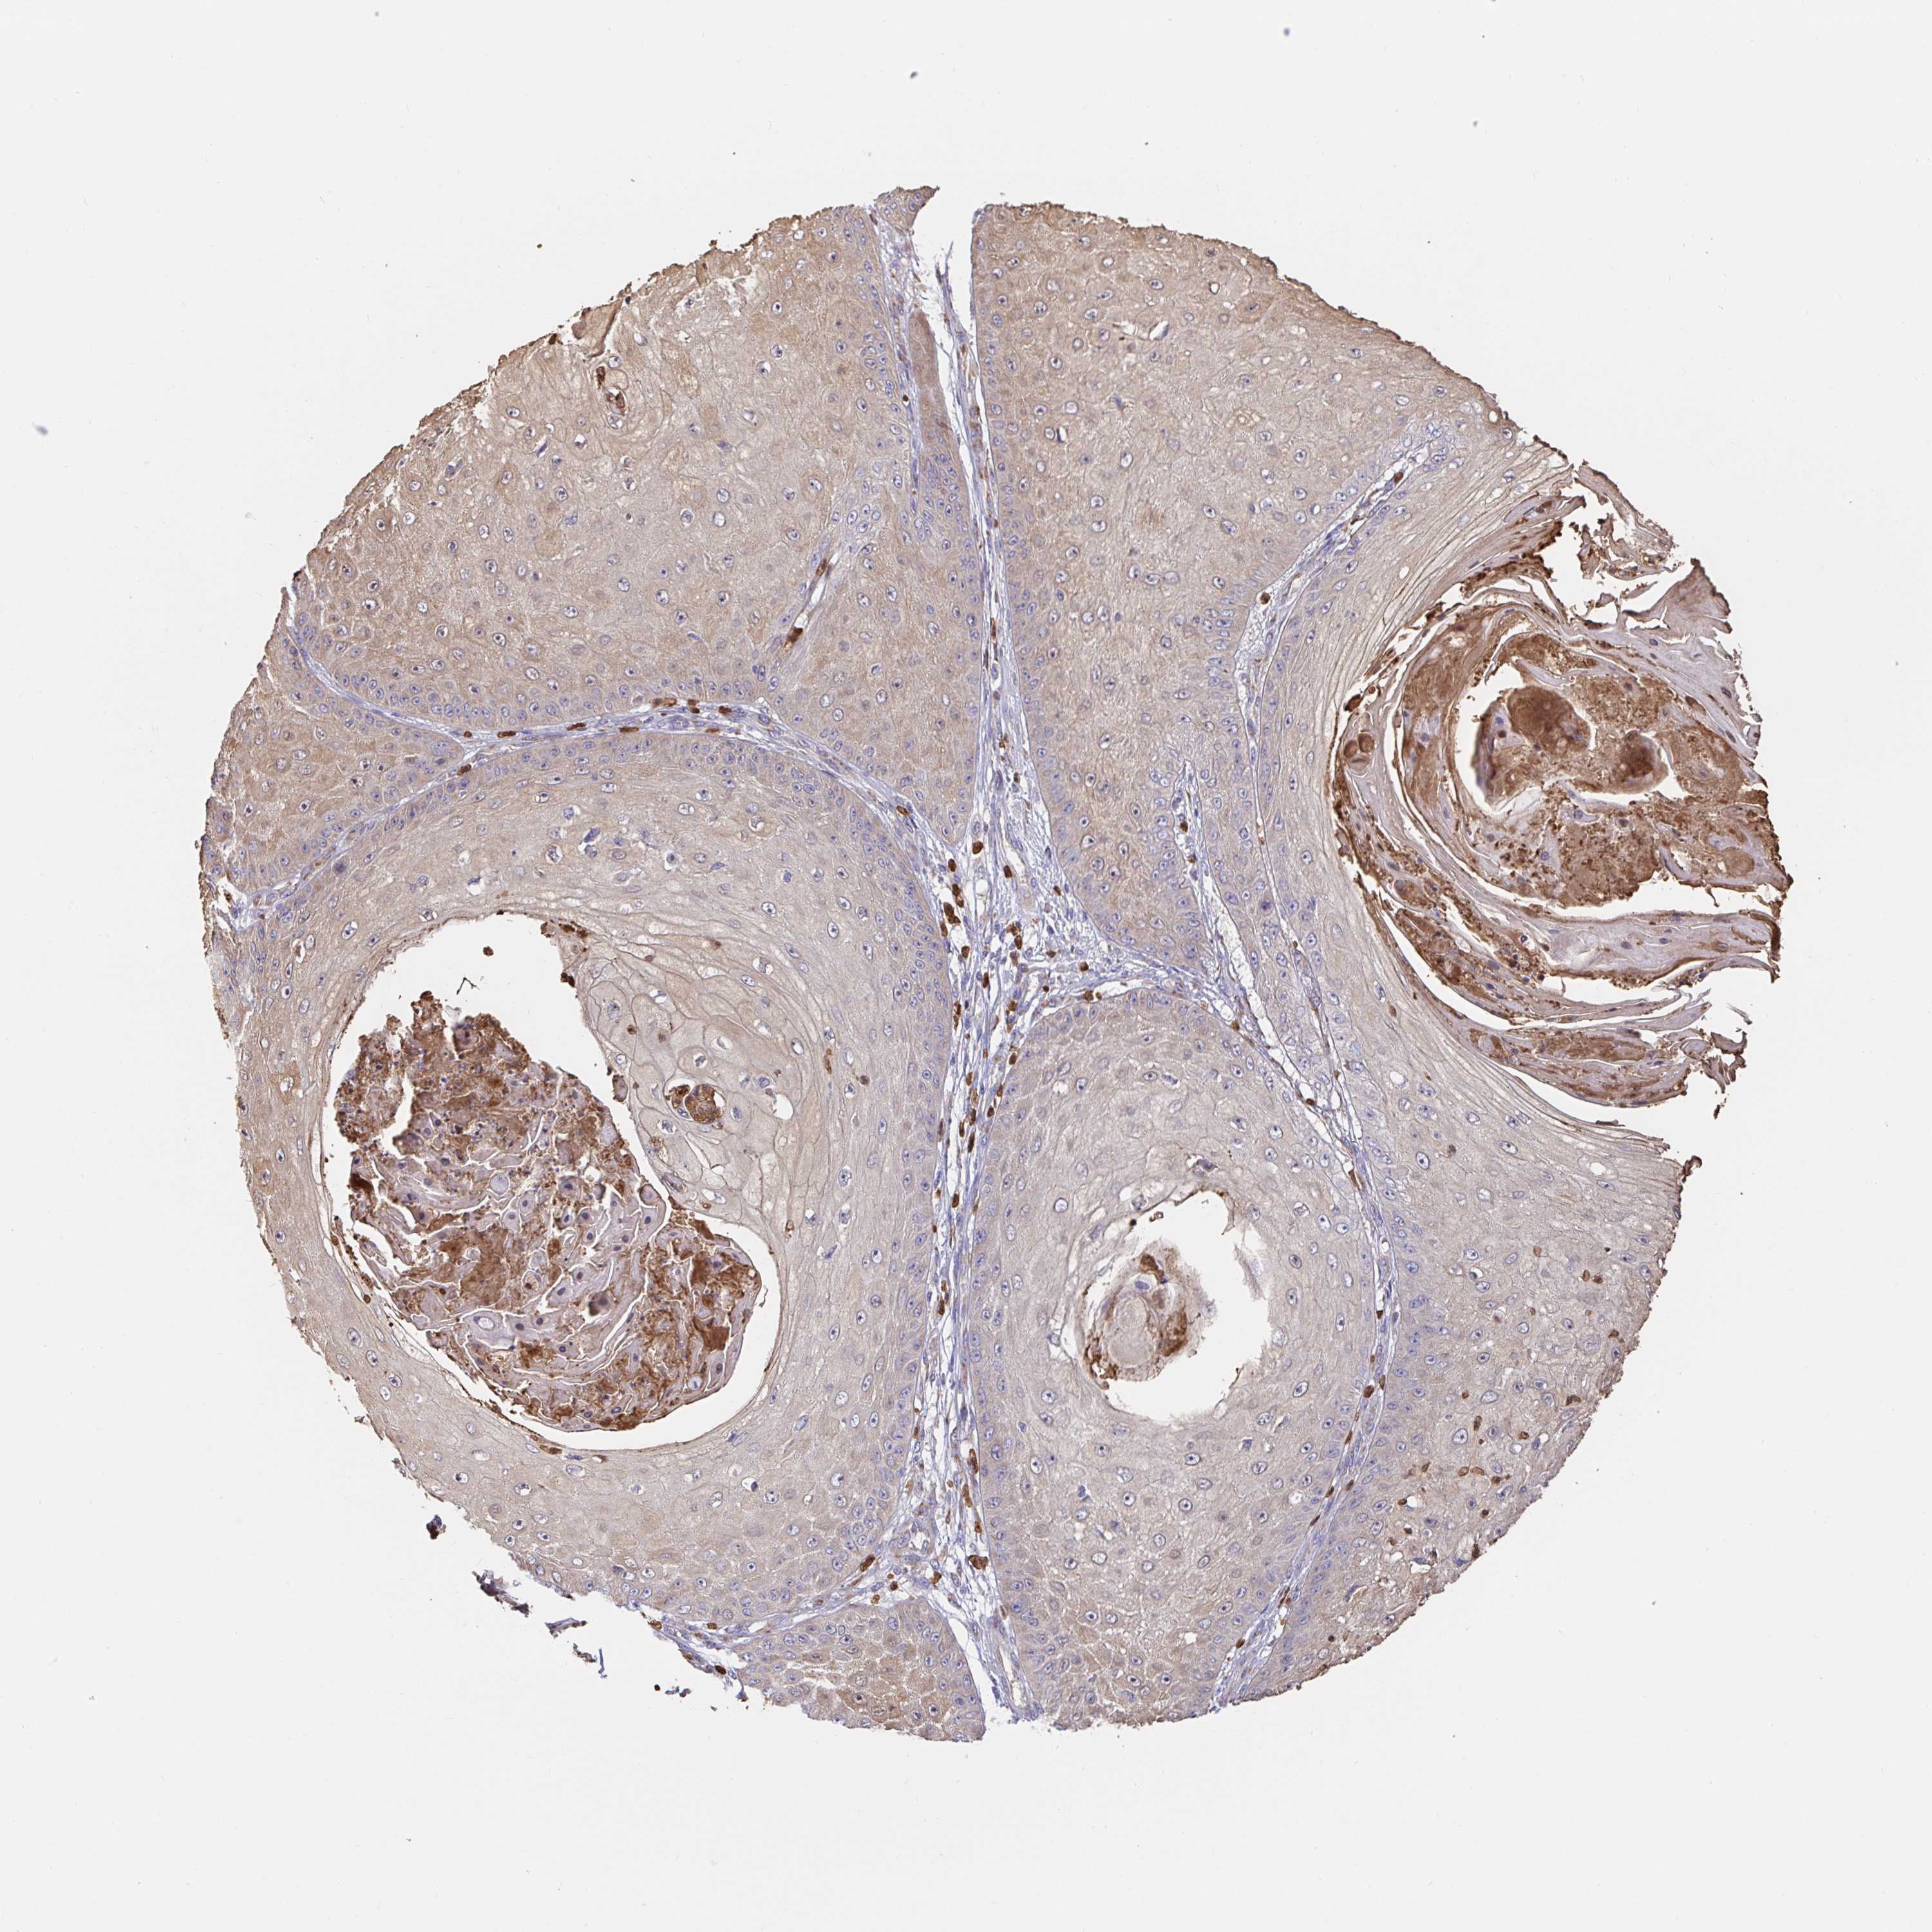

SKIN CANCER - Protein expressioni

A mouse-over function shows sample information and annotation data. Click on an image to view it in a full screen mode. Samples can be filtered based on level of antibody staining by selecting one or several of the following categories: high, medium, low and not detected. The assay and annotation is described here.

Antibody stainingi

Antibody staining in the annotated cell types in the current human tissue is reported as not detected, low, medium, or high, based on conventional immunohistochemistry profiling in selected tissues. This score is based on the combination of the staining intensity and fraction of stained cells.

Each image is clickable and will lead to virtual microscopy that enables deeper exploration of all samples and also displays staining intensity scores, fraction scores and subcellular localization as well as patient and tissue information for each sample.

Antibody HPA035199

Antibody CAB004272

Staining

High

Medium

Low

Not detected

Intensity

Strong

Moderate

Weak

Negative

Quantity

>75%

75%-25%

<25%

None

Location

Nuclear

Cytoplasmic/membranous

Cytoplasmic/membranous,nuclear

Basal cell carcinoma

Squamous cell carcinoma, NOS